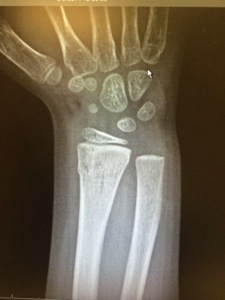

I feel like at any minute the police are going to show up and haul me to jail. I mean, my kid says her arm hurts and I tell urgent care “she fell off the monkey bars”. It is the most common childhood injury ever but the nurse looked at me like I was joking. No really, at the park yesterday she thought she could do the monkey bars by herself and plop landed on her wrist and back.

We gave it a good 20 hours and things weren’t improving so here we are waiting at the local urgent care. We have been waiting over an hour and they don’t seem to be in a rush to get us out of here.

It’s clear the doc doesn’t think it is broken and I didn’t see anything on the X-rays but I am certainly not a radiologist! I can’t decide if I hope it is broken to justify spending the $50 copay and 2 hours of my life or if I want it to be okay so we can get out of here!

I missed a call from the urgent care the next morning. The voicemail said, “We have made an appointment at the orthopedist for 1pm today for your daughter. Please call us with any questions.” Um, yes I have questions! When I called they said that when the radiologist was filing the final report he saw a break and we need to see ortho. Um, okay, but now it is Monday morning and I just send my kid to school with a broken arm and told her to be brave!

Ignoring the possible incompetence, we finally made it through orthopedics yesterday afternoon and my sweet girl now sports a very pretty purple cast. And the best part – it is waterproof! Yippee for mommy and daddy!

This is the x-ray, the break is in the larger bone in her arm at the top – on the left side of this bone, you’ll see a little spot that protrudes, this is the classic presentation of a buckle fracture. The break goes all the way across her bone right there.Â